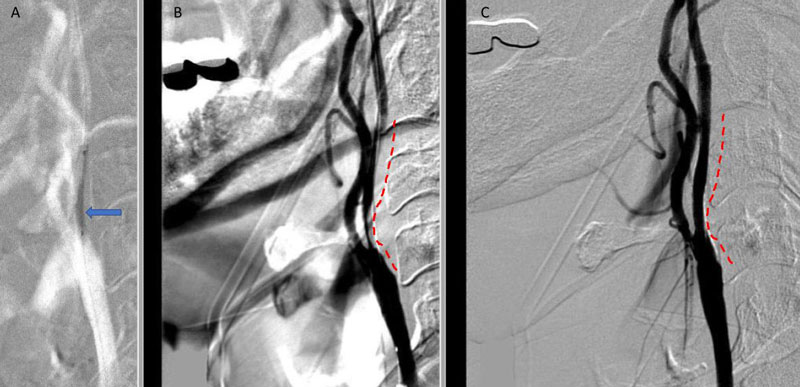

On admission, her initial CT scan was negative for stroke or hemorrhage, however a CTA demonstrated severe high grade 99% stenosis of the right Carotid bulb (ICA) with markedly diminished caliber of the cervical intracranial carotid artery secondary to calcified atherosclerosis without evidence of dissection (Figure 1).

Figure 1. A and B) CTA demonstrating severe ICA 99% stenosis (dotted) with flow-reduced diminution relative to the left ICA (red arrows) and distal plaque extension to C2 level.